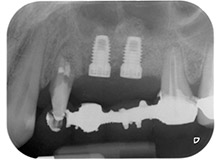

Fig. 1 : Patiente de 58 ans. Radio pré-opératoire montrant une lésion du parodonte apical à la dent 24 et une perte horizontale d'os alvéolaire dans le deuxième quadrant.

Une patiente de 58 ans se plaignait de douleurs et d'une mobilité accrue de la dent pilier 24 de son bridge. Présence d'une inflammation parodontale avec formation de poches de 7 mm de profondeur dans le sens mésiobuccal et de plus de 12 mm dans le sens distal, ainsi que d'une atteinte de la furcation au troisième degré. La radiographie a par ailleurs révélé une lésion parodontale étendue autour de la région apicale de la dent 24 ayant préalablement reçu un traitement endodontique (alio loco) (Fig. 1).